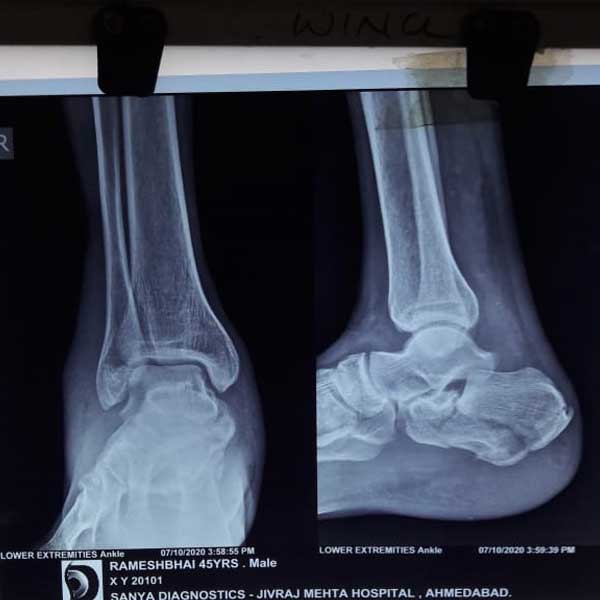

Case:19 Percutaneous fixation with Implants

A male patient, aged 78 years had been diagnosed to have a closed Pott’s fracture Left Ankle. He was treated operatively with Percutaneous fixation with Implants.

Pre-Operative

Post-Operative